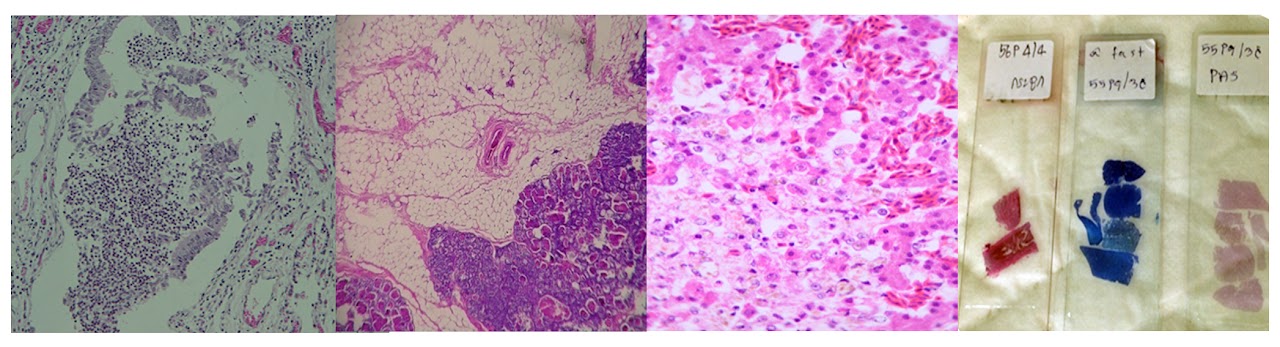

การตรวจหา Inclusion body ของเชื้อ Porcine Circovirus จากอวัยวะในระบบน้ําเหลืองสุกรโดยวิธีทางพยาธิวิทยา

ห้องปฏิบัติการจุลพยาธิวิทยา (necropsy)

ห้องปฏิบัติการอิมมูโนพยาธิวิทยา (Immunohistology)